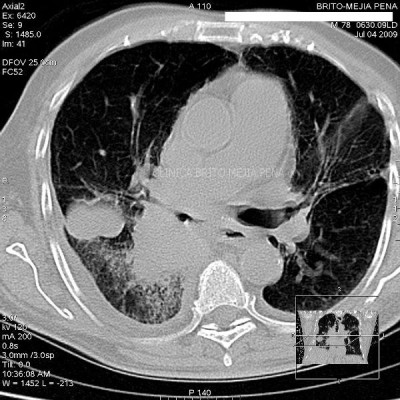

Fibrosis y enfisema pulmonar